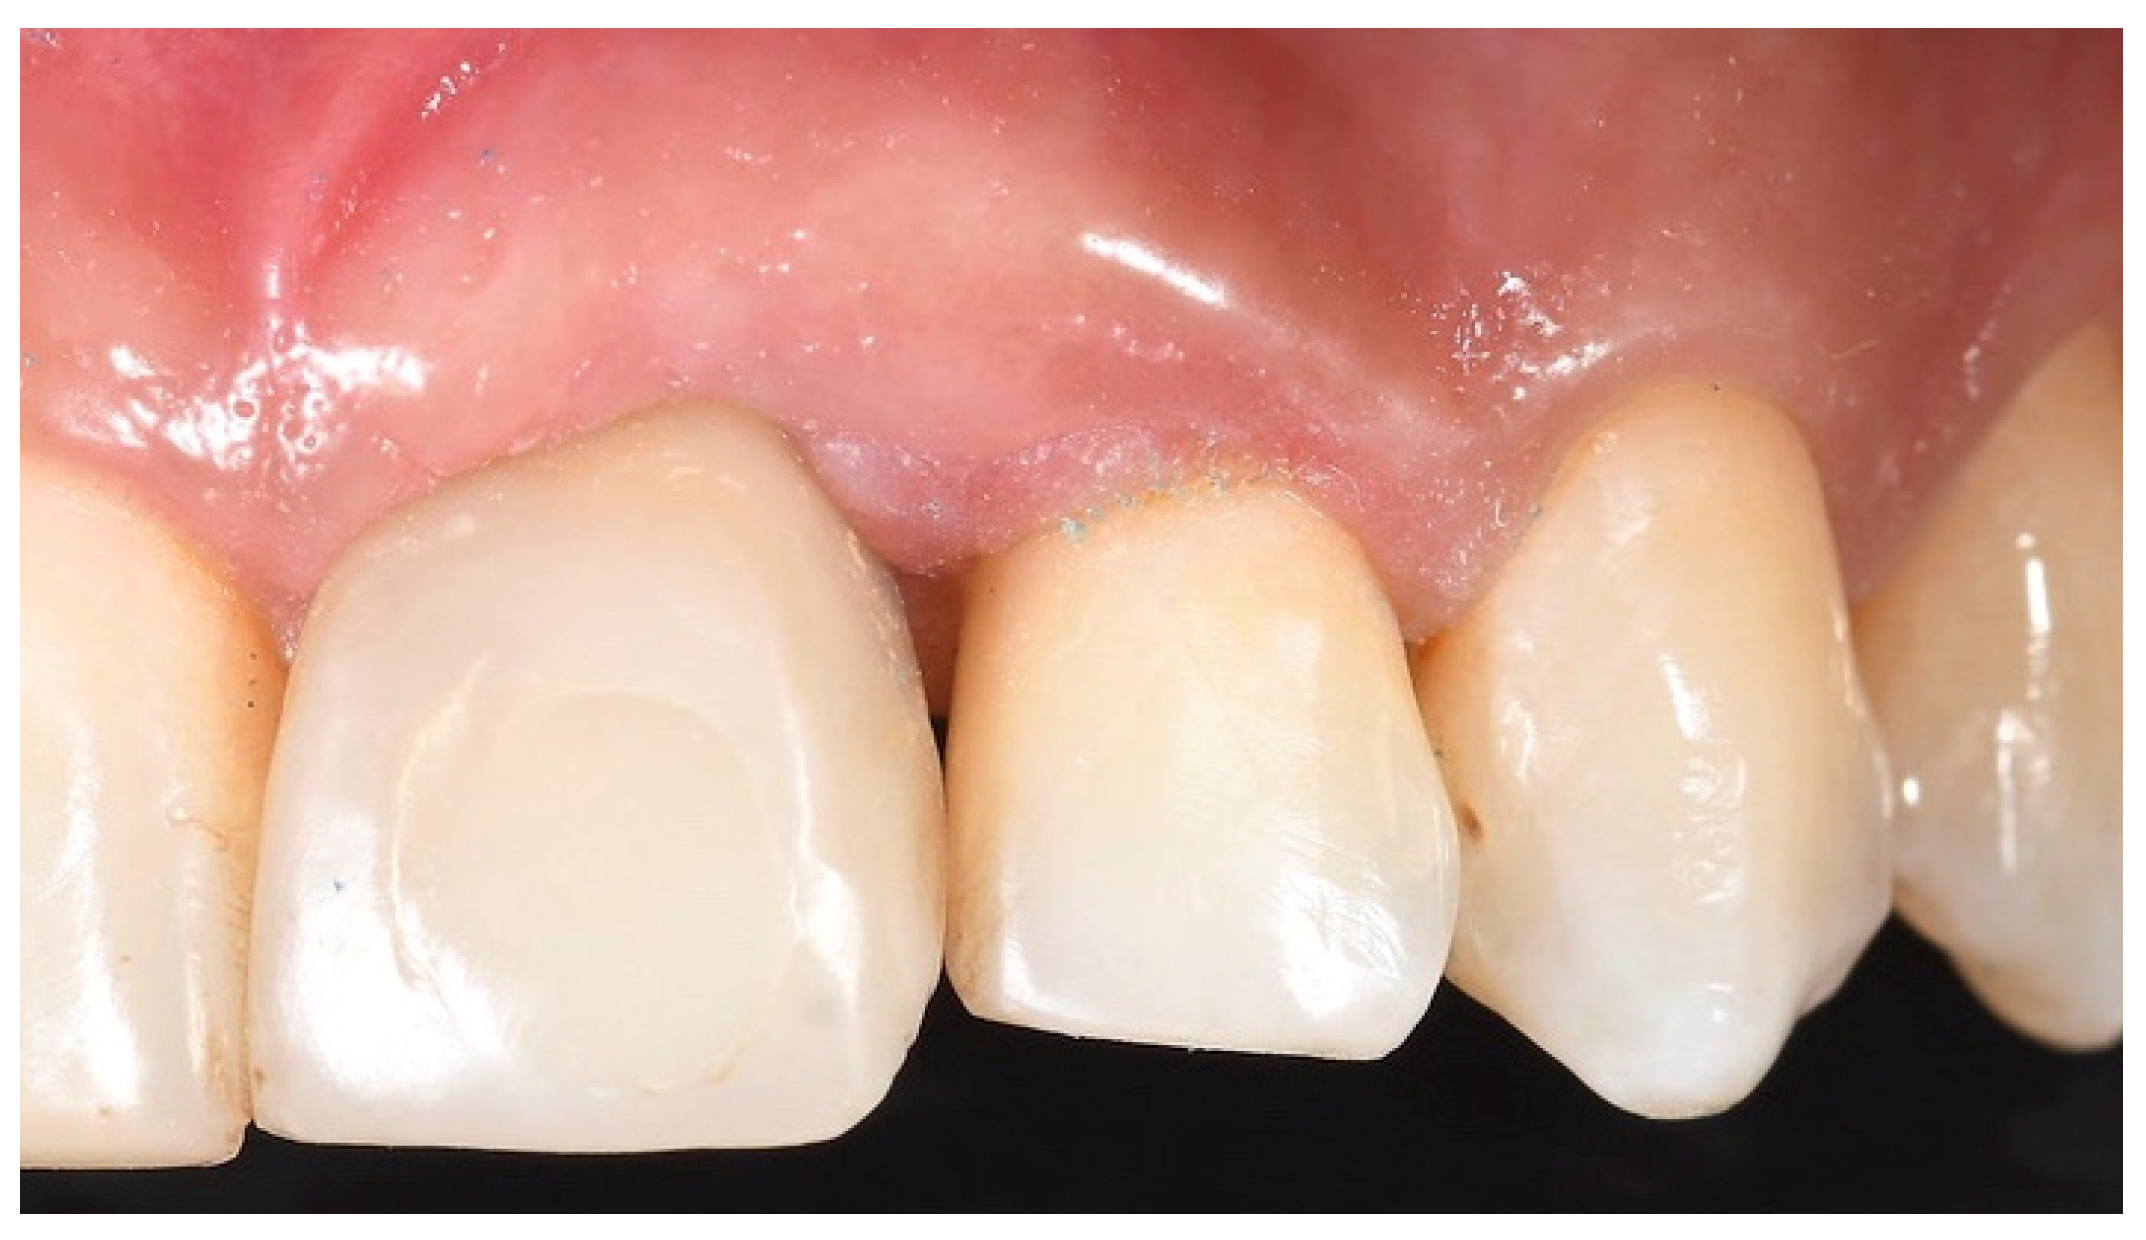

Tissue Recession around a Dental Implant in Anterior Maxilla: How to Manage Soft Tissue When Things Go Wrong?

2. Case Presentation